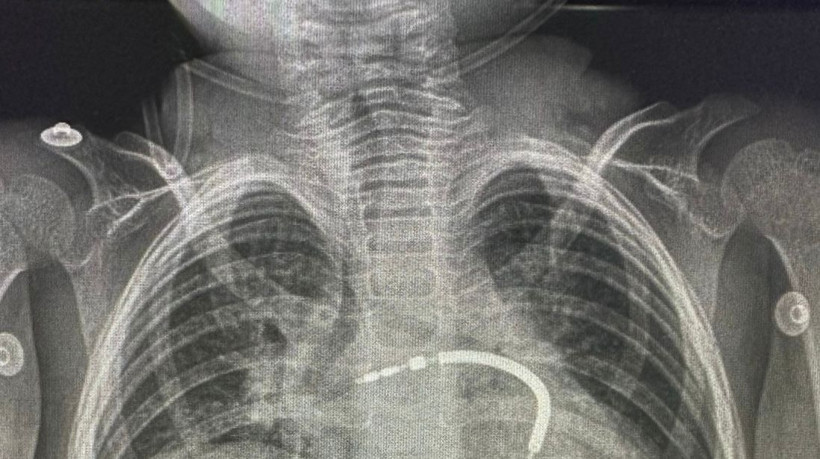

A operação aconteceu no Hospital Luís França, da Hapvida

A operação aconteceu no Hospital Luís França, da Hapvida Crédito: Divulgação / Hapvida